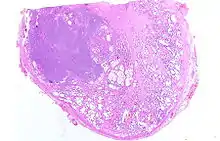

Adénocarcinome prostatique

Adénocarcinome ; tissus indifférenciés

Anatomopathologie

Le cancer entreprend la portion périphérique de la glande, au contraire de l'hypertrophie prostatique bénigne qui intéresse la zone centrale, périurétrale.

La gravité de l'évolution est corrélée avec l'aspect microscopique (score de Gleason), le niveau de PSA et l'extension de la maladie[53].